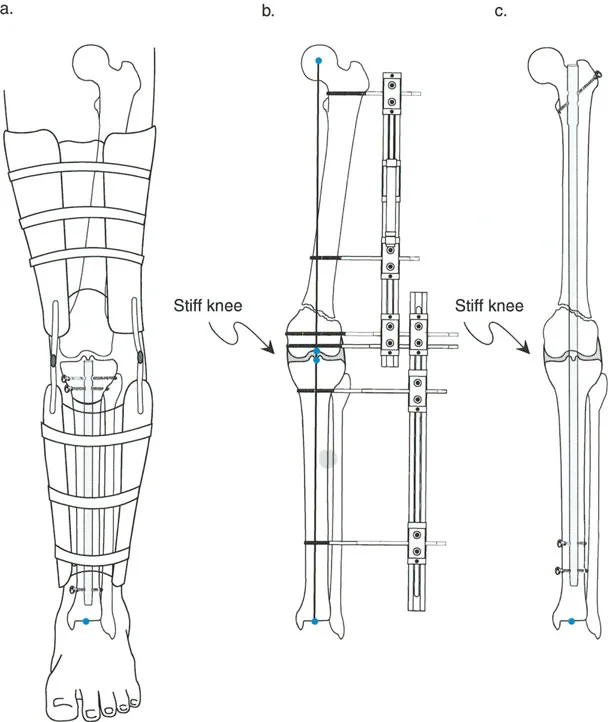

- مثبتات إليزاروف الدائرية الكلاسيكية: تتكون من حلقات معدنية متصلة بالعظم بأسلاك رفيعة، وتسمح بتصحيح متعدد المستويات.

المفصلات القريبة من المفصل وقواعد قطع العظم (Osteotomy Rules)

عند التعامل مع التشوهات الواقعة بالقرب من خط المفصل - مثل التقوس الشديد في الجزء العلوي من الساق (مرض بلونت) أو التشوه الفحجي في الجزء السفلي من عظم الفخذ - يصبح وضع الجهاز مقيدًا هندسيًا. إن المتطلبات البيولوجية للحفاظ على كبسولة المفصل، وتجنب وضع الأسلاك داخل المفصل، ومنع التهاب المفاصل القيحي، غالبًا ما تجبر الجراح على وضع الحلقة المرجعية على مستوى مختلف تمامًا عن مركز دوران الانحراف (CORA) الفعلي.

تحدي مركز دوران الانحراف (CORA) القريب من المفصل

لمطابقة مفصلة المثبت الخارجي مع المستوى الدقيق لمركز دوران الانحراف (CORA)، يجب غالبًا بناء المفصلة فوق أو تحت مستوى الحلقة الفعلية. يُعرف هذا في مبادئ بالي باسم تجميع المفصلة القريبة من المفصل (juxta-articular hinge assembly).

إذا كان مركز دوران الانحراف (CORA) يقع بالقرب من خط المفصل، فإن وضع حلقة إليزاروف القياسية عند هذا المستوى بالضبط مستحيل دون انتهاك مساحة المفصل أو شد الهياكل الكبسولية الحيوية. لذلك، يتم تثبيت الحلقة المرجعية بالعظم الكثيف أو العظم الطويل المتاح، ويتم بناء آلية المفصلة باستخدام قضبان ملولبة، ولوحات توصيل، ودعامات. ثم يتم "إنزالها" (أو رفعها) لتتطابق تمامًا مع مركز دوران الانحراف (CORA) الهندسي الحقيقي.

في المنشآت القريبة من المفصل، غالبًا ما نعتمد على قاعدة قطع العظم 2. نظرًا لأنه لا يمكننا قطع العظم بأمان عند خط المفصل تمامًا (مركز دوران الانحراف CORA)، فإننا نقطع العظم في مستوى أدنى في منطقة الميتافيسيس. بعد تحقيق التصحيح الزاوي عبر المفصلات (محور تصحيح الانحراف ACA)، يتم إعادة محاذاة خطوط المحور الميكانيكي بشكل مثالي، ولكن نهايات العظم في موقع قطع العظم تتحرك بالنسبة لبعضها البعض.

قيود الأسلاك والدبابيس في القاعدة 2

لتحقيق هذه الترجمة الضرورية والمقصودة بسلاسة باستخدام إطار دائري كامل الأسلاك، يلزم استخدام أسلاك الزيتون المعاكسة (counter-opposed olive wires). تعمل أسلاك الزيتون كقوى سحب ديناميكية، تسحب قطعة العظم على طول الحلقة أثناء فتح المفصلات. بدون أسلاك الزيتون، سيبقى العظم ثابتًا بينما تتحرك الحلقة عبر الأنسجة الرخوة، مما يسبب نخرًا شديدًا في الجلد.

على العكس من ذلك، إذا تم استخدام دبابيس نصفية (مسامير شانز)، فإنها تقيد العظم بطبيعتها بالحلقة. نظرًا لأن الدبابيس النصفية هي أذرع صلبة (مثبتة من طرف واحد بالحلقة ومغروسة في العظم من الطرف الآخر)، فإنها لا تسمح للعظم بالانزلاق على طول محور السلك. هذا يجعل أسلاك الزيتون غير ضرورية للترجمة في منشآت الدبابيس النصفية، ولكنه يتطلب من الجراح التأكد من أن الدبابيس النصفية قوية بما يكفي (عادةً دبابيس بقطر 5 مم أو 6 مم مطلية بهيدروكسي أباتيت) لتحمل لحظات الانحناء الناتجة عن الترجمة.